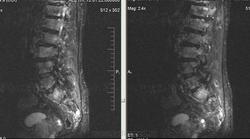

Метастазы рака простаты, кроме измений в позвонках видна сама первичная опухоль и лимфатические узлы (общий и наружный подвздошные слева, ещё один в левой подвздошной ямке).

После добавления томограмм исследования органов малого таза картина стала ещё печальнее...

Да, запустил пациент. До этого были проблемы с мочеиспусканием, рези, болезненность. Лечился самостоятельно от простатита, отмечал временное улучшение.